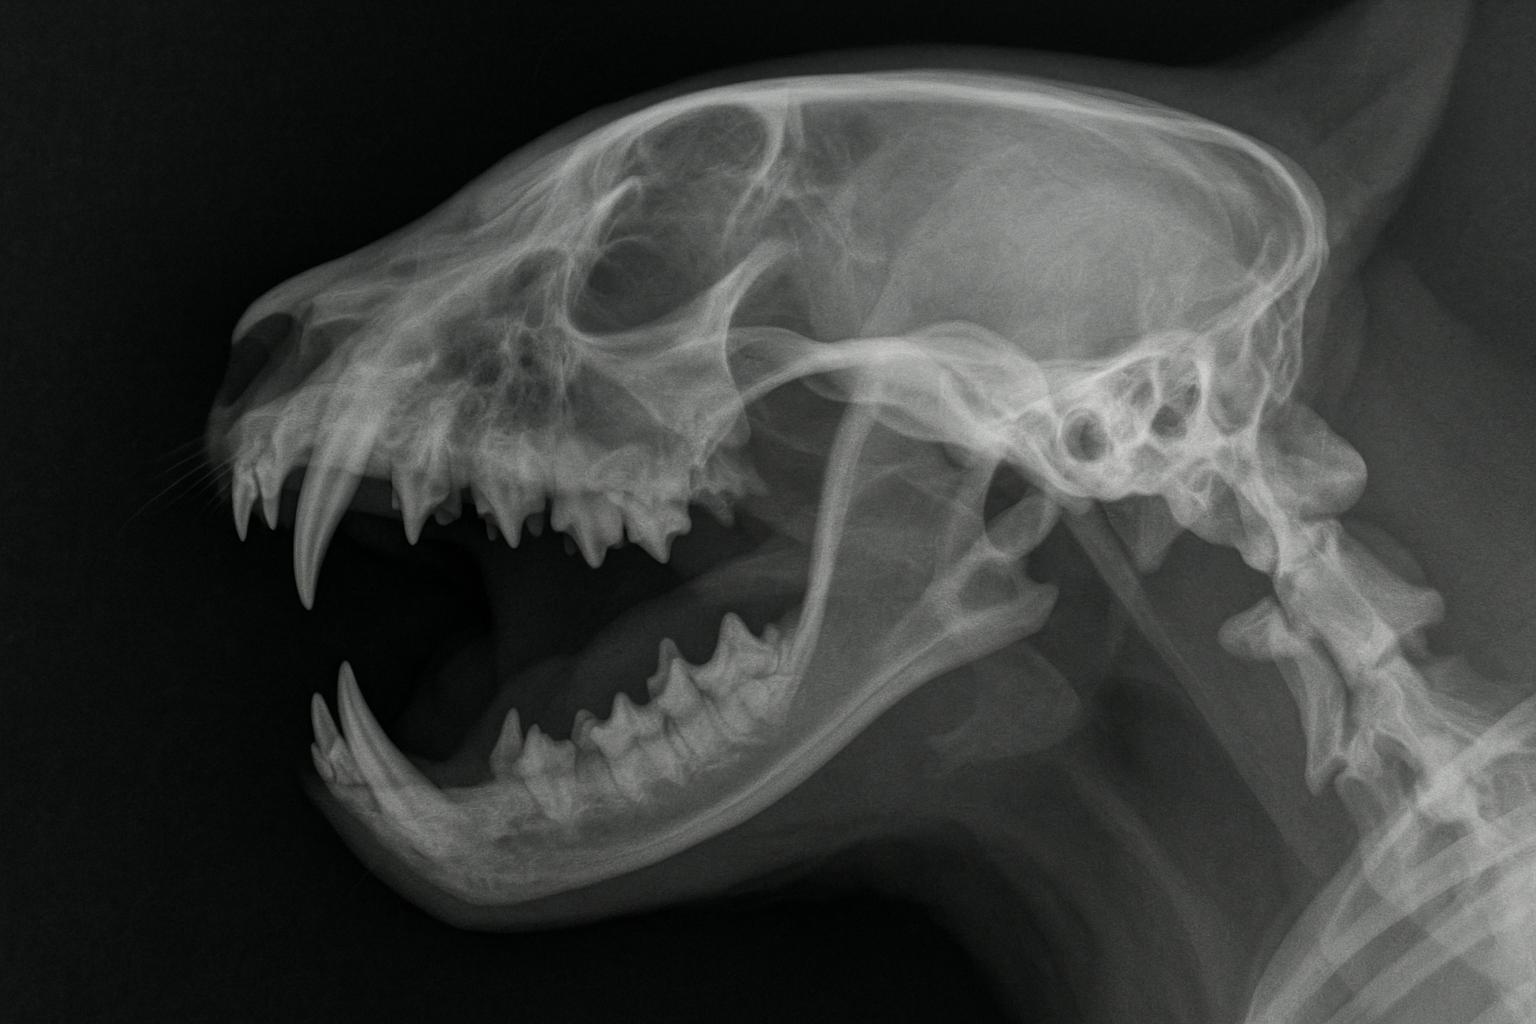

El diagnóstico de esta enfermedad se realiza mediante una exploración bucal, complementada con radiografías dentales en los casos más severos, para valorar si existe algún cuadro más grave, como periodontitis o gingivoestomatitis crónica felina. El tratamiento incluye el uso de fármacos, cambios en la higiene dental y limpiezas dentales profesionales. Además, existen medidas preventivas que ayudan a evitar la enfermedad. Si quieres conocer más sobre la gingivitis felina, sus síntomas, contagio y cómo actuar ante un gato afectado, continúa leyendo este artículo de ExpertoAnimal.

En muchos casos, también se recomiendan radiografías dentales para valorar los tejidos y las raíces de los dientes, lo que permite detectar periodontitis o resorción dental. Además, si se sospecha que la gingivitis pueda estar relacionada con enfermedades infecciosas virales, se pueden solicitar análisis de sangre y pruebas específicas para detectar estos virus.